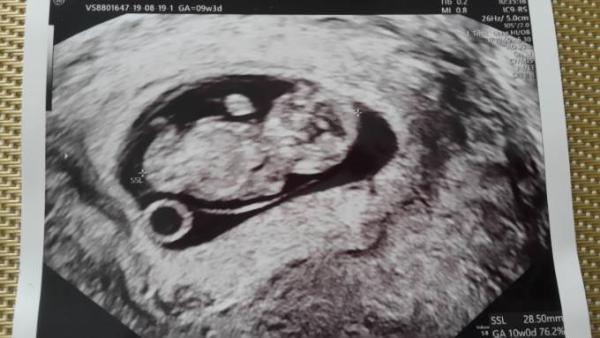

Huhu heute war es wieder soweit. Das babykino. Es sieht alles sehr gut aus das Ultraschallgerät zeigte 9+5 an also ET 2.4 statt 4.4 , mal sehen ob die Ärztin das so einträgt , geturnt hat es und das Herzchen hat fleißig geschlagen.. Die Ärztin meinte nur ich soll Aspirin nehmen damit es nicht wieder zu Plazenta Problemen kommt am Ende der Schwangerschaft. In 2 Wochen soll ich nochmal kommen, da wird eine praenatal Diagnostik gemacht, dadurch das unser Sohn so schwer krank war am Anfang, wollen wir einfach sicher gehen.. so das war es dazu .. ein Foto noch dabei und wir haben heute Geschenke bekommen von der Frauenärztin. Eine flasche von mam und ein schnuller darin

Bild zu Ultraschalltermin .. muss hier auch jemand Aspirin nehmen ? - Forum für April - Mamis